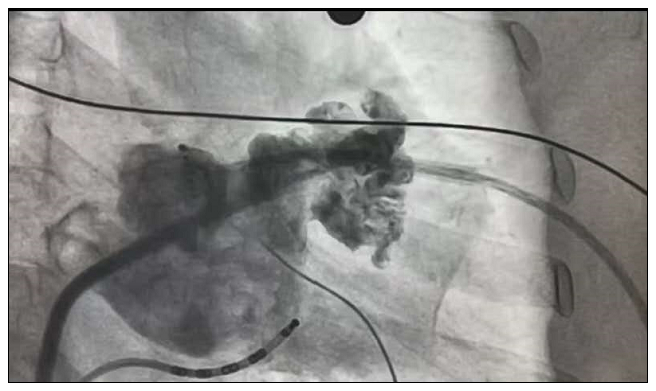

5月28日,汪杰主任以及手术团队经过近4个小时的努力,巧妙地利用了一站式的左心耳封堵和房颤射频消融治疗房颤的双介入手术。两个步骤衔接有序、一气呵成,成功完成了铜陵地区首例房颤一站式手术。

左心耳封堵术是近几年新兴出现的房颤患者预防血栓的技术,对于抗凝药物有禁忌或不能耐受抗凝药物的患者是一种新的治疗方式。它创伤小、恢复时间短,能显著提高患者生活质量,手术安全性较高。对于房颤症状明显的患者,抗凝治疗后出血风险高、不适合长期服用或可能存在消化道出血、脑出血,以及不愿意服药患者,“一站式”房颤射频+左心耳封堵治疗技术为此类患者带来福音。此项先进的疾病复合治疗模式,其优势是一次手术达到两个治疗目的,使患者免受第二次手术痛苦。